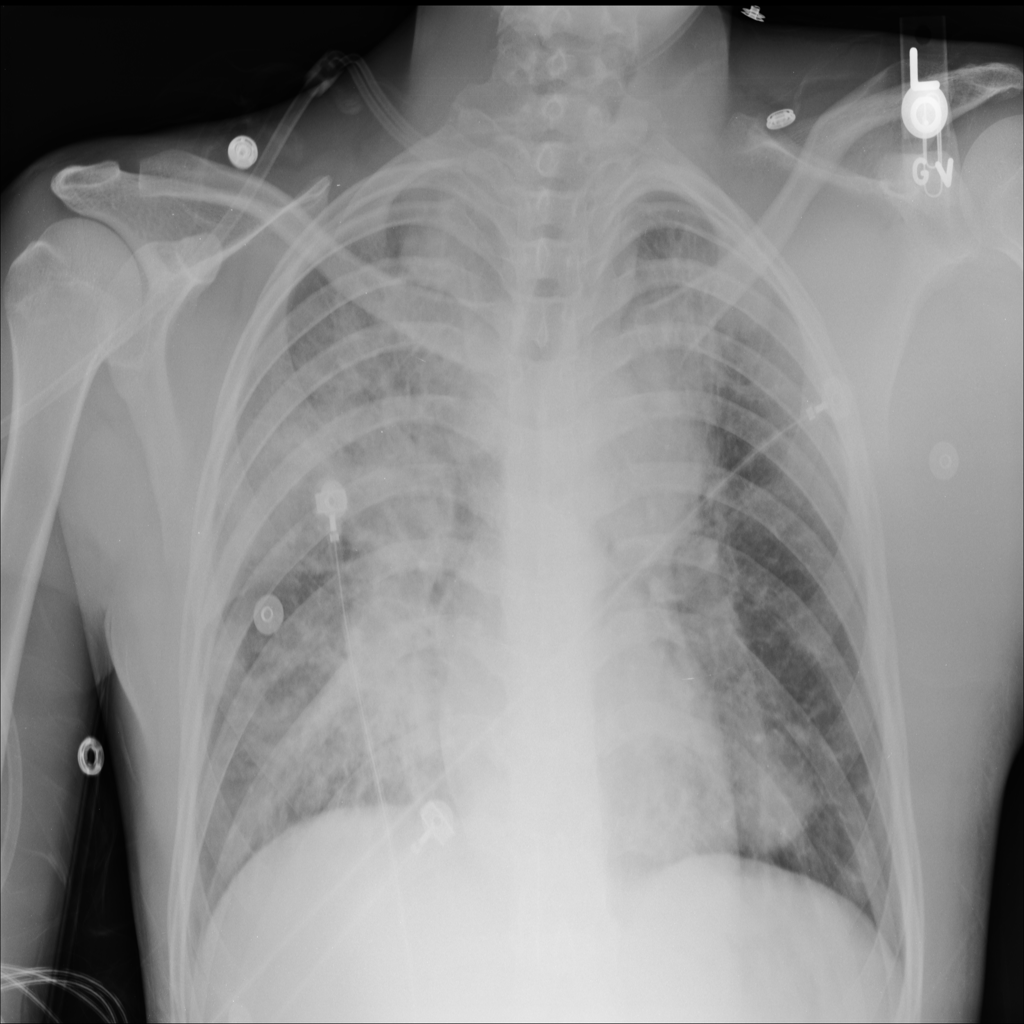

PAT-EBE1 · IMG-019Pneumonia

PAT-EBE1 · IMG-019

AP